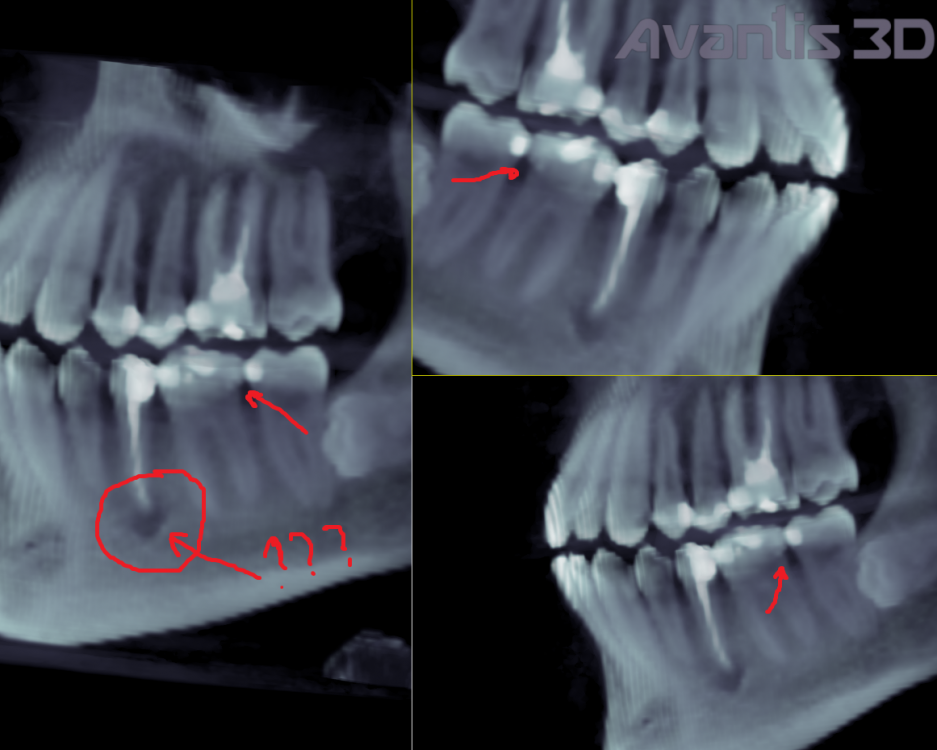

amkazan Опубликовано 14 июля, 2022 Поделиться Опубликовано 14 июля, 2022 Здравствуйте, между 6 и 7 зубом слева появилась чувствительность на воду комнатной температуры. Боль не ужасная, но скорее ощущение весьма чувствительное, проходит через некоторое количество секунд 1) Сначала думал из-за кариеса в 7ке. Залечили. Не прошло 2) Потом подумал что из-за зуба мудрости 8ки горизонтального. Удалили. Не прошло 3) Потом уже обратился к КТ и вот смотрю : Может ли это быть из-за некой полости или некой трещины в 6ке, которая указана стрелочками на 2х приложенных скриншотах? (Я не стоматолог, что сам принимаю решения как мне лечиться. Просто ситуация сложилась такая, что я постоянно перемещаюсь по городам и не могу лечиться у одного стоматолога и поэтому приходится самому пытаться разбираться и просить помощи по совету) Прошу у вас помощи.?Разобраться Прикладываю КТ (это был Vatech, думаю Pax-i3D как самый распространённый, но не факт) в формате DCM на google диске и на Яндекс диске https://drive.google.com/file/d/1vPTicAzKgWuJWQIRL_fG968K7VONyEou/view?usp=sharing https://disk.yandex.ru/d/3vmKZGk3sydIqw p.s. Заодно хочу спросить вопрос а что это за полость под 5кой??? Смотрю на снимки от 2018го. Она там уже есть. Была ли раньше неизвестно.. Ссылка на комментарий

Женька Опубликовано 14 июля, 2022 Поделиться Опубликовано 14 июля, 2022 Здравствуйте. Полость под 5-выход из костной ткани ментального нерва (нормальная анатомия, делать ничего не нужно с этим) Ваш 6 практически полностью состоит из пломбы, надо как минимум проверить прилегание этих самых пломб. Ну и пожалуй закрыть его коронкой, чтобы не сломался глубже и безвозвратно. Боли могут быть как раз следствием выше сказанного. 1 1 Ссылка на комментарий